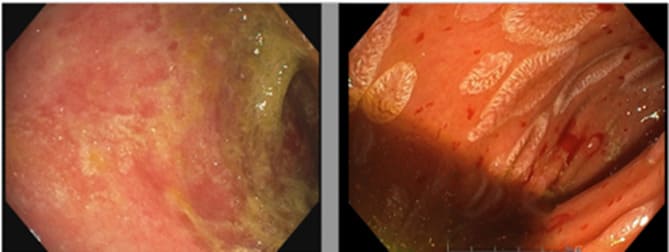

Figure 2: Endoscopic images of the duodenum. On the left (d+38) before mesenchymal cell administration, showing mucosal atrophy, absence of villi and fibrin deposits. On the right (d+70) and D+23 after the first injection of MSCs, revealing islands of re-epithelialization despite mucosal hemorrhagic fragility.

Eighteen days after the first MSC-FFM infusion (D+18), we observed a partial resolution with a decrease of gastrointestinal-aGvHD from grade IV to grade III, which was reflected in a decrease in blood transfusions and endoscopic clot removal. Endoscopic evaluation and histology performed on D+23 showed focal duodenal re-epithelialization, co-existing, however, with areas of ulceration on D+23 (Figure 1, C and B; Figure 2). The evolution continued to be favorable with a transient complete clinical remission on D+79 (Figure 3). The diarrhea and bleeding resolved completely. A persistent abdominal discomfort prevented a complete resumption of oral feeding and induced persistent need for parenteral nutrition. From D+97, during the attempt to start enteral nutrition, the patient’s digestive losses slightly increased, with values mostly consistent with a grade I GI-GvHD until the end of his life (Figure 3).